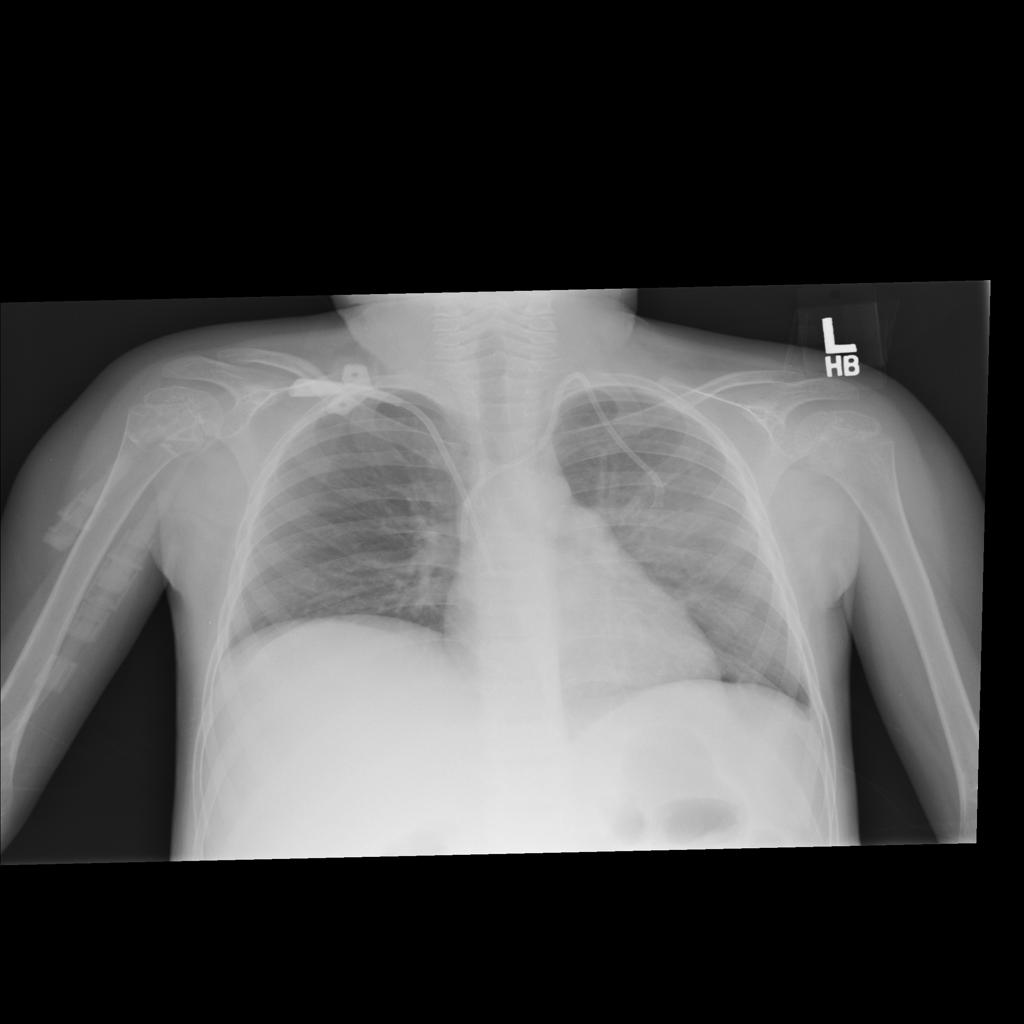

PAT-A380 · IMG-002Consolidation

PAT-A380 · IMG-002

AP